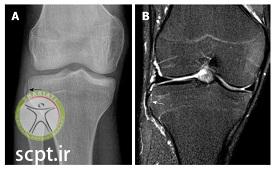

رادیوگرافی یا روش عکسبرداری ایکس ری توانایی نشان دادن پارگی رباط صلیبی را ندارد ولی میتواند عوارض استخوانی و همچنین شکستگی ها را نشان دهد و لذا بهترین روش برای تشخیص پارگی رباط صلیبی ام آر آی است.

علائمی از فشردگی و کمپرس فراکچر در فمور بخش لترال کندیل آن مشاهده میشود. ( این حالت متفاوت از Deep sulcus sign موجود در رادیوگرافی حالت درازکش قفسه سینه در افراد نموتوراکس است )